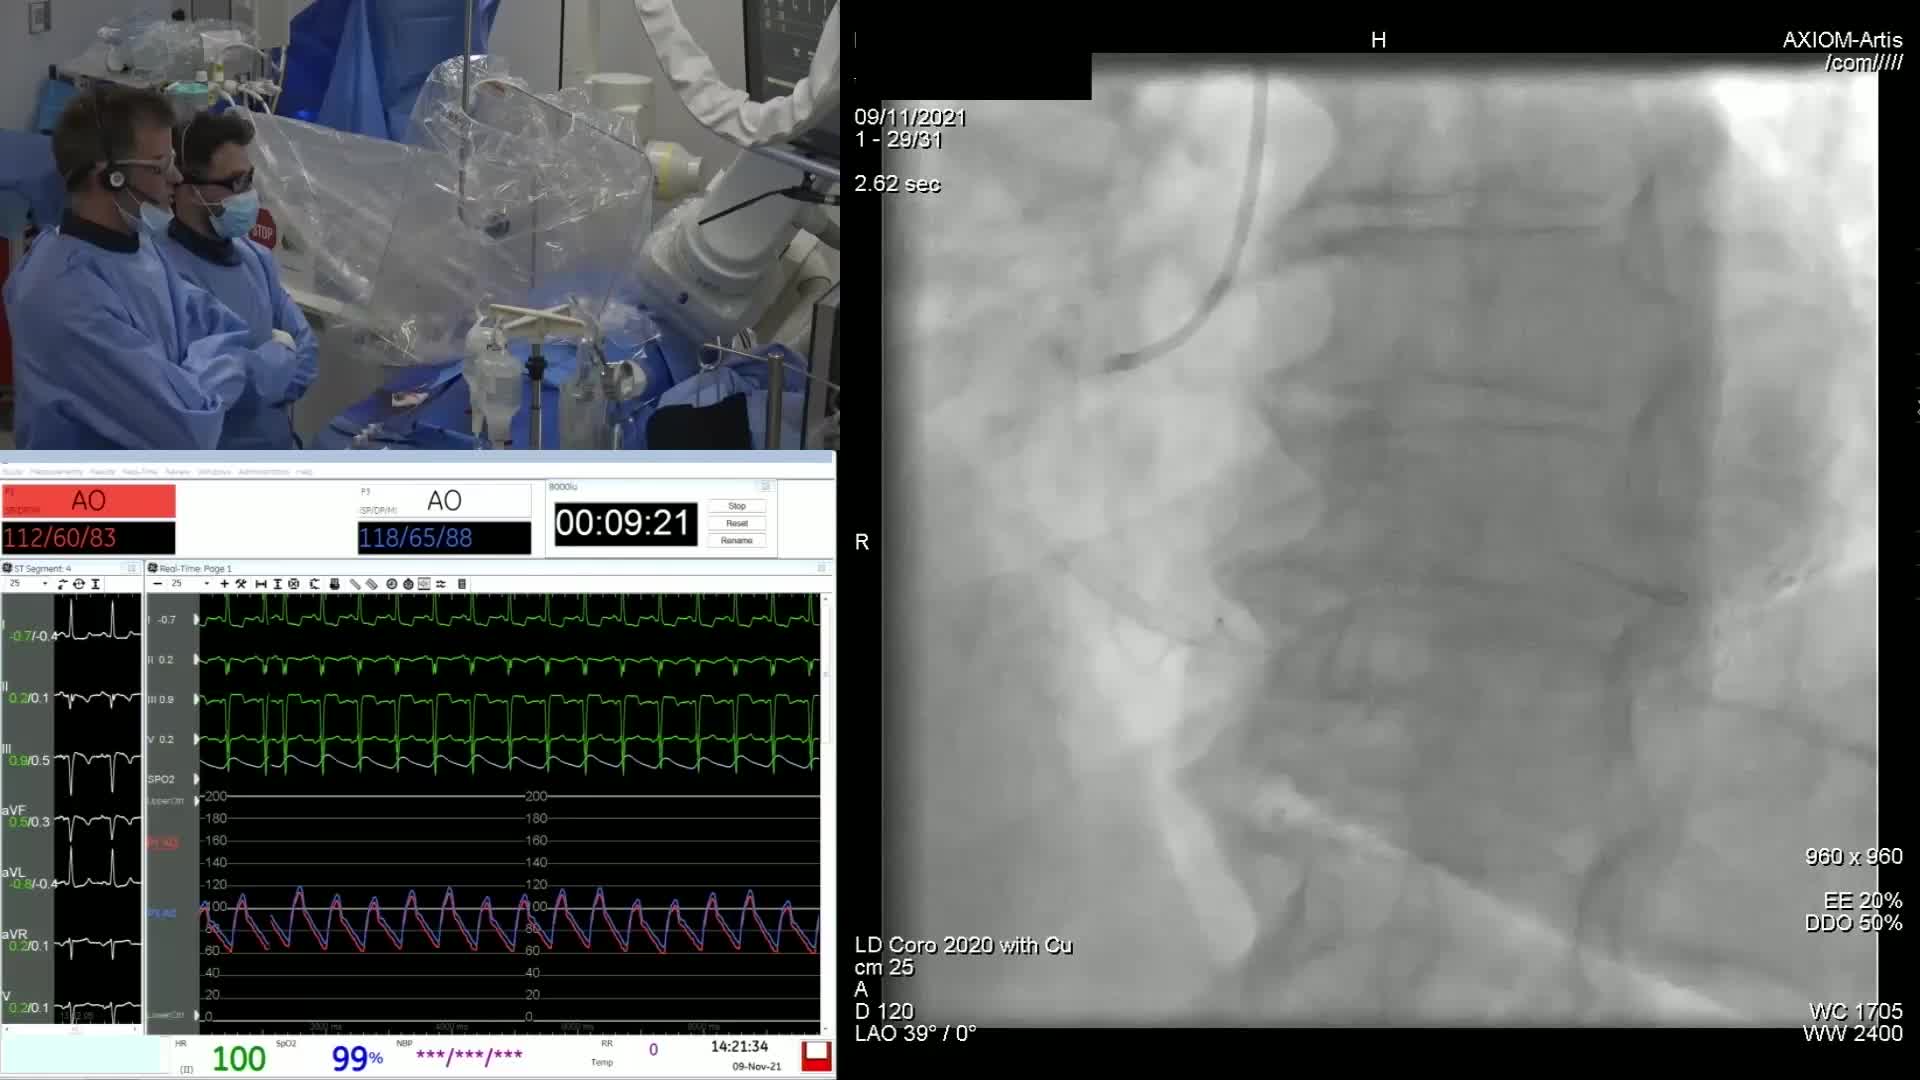

Gulf-Optimal Chronic Total Occlusion: Bahrain Event - Day 1

Gulf-Optimal Chronic Total Occlusion: Bahrain Event - Day 2

Gulf-Optimal Chronic Total Occlusion: Live Case Follow Up